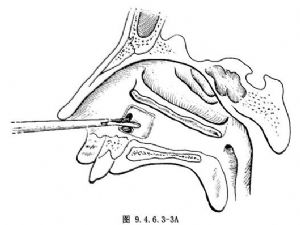

再用Luc咬骨鉗咬去穿刺的後上及後下骨壁(圖9.4.6.3-3)。